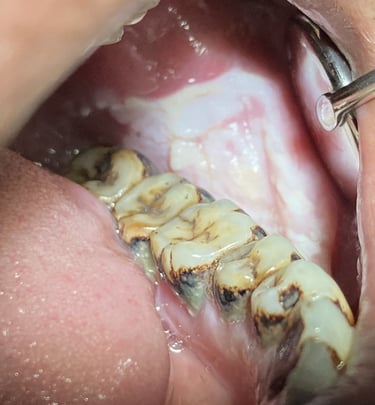

Gentle tooth removal

When a tooth is too damaged to be saved, our gentle approach and meticulous technique ensures the removal is as comfortable as possible, prioritizing your overall oral health and well-being.